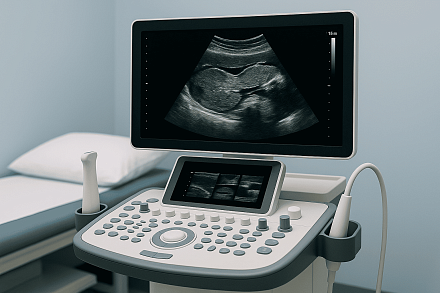

УЗИ органов брюшной полости — это эффективный и безопасный метод диагностики, который позволяет подробно оценить состояние печени, желчного пузыря, поджелудочной железы, селезенки и других внутренних органов. Комплексное ультразвуковое исследование помогает выявить воспалительные процессы, камни, опухоли и другие патологии на ранних стадиях.

В Центре здоровья НЛМК УЗИ проводится с использованием современного оборудования, что обеспечивает высокую точность результатов и комфорт для пациента. Исследование органов брюшной полости вместе с почками особенно полезно для комплексной оценки состояния мочевыделительной системы и выявления сопутствующих заболеваний.